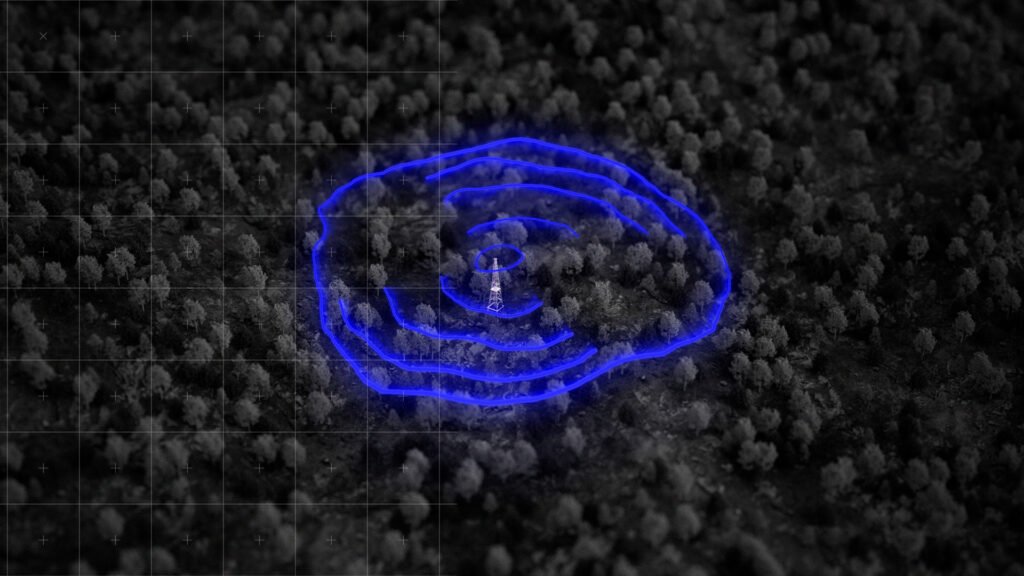

El dispositivo inteligente está diseñado para operar donde la tecnología

convencional no llega. Cerca de 200.000 personas mayores viven sin acceso a

las comunicaciones modernas; este pastillero aprovecha la tecnología

LoRaWAN, utilizando la red de antenas y torres de radio ya existentes en el

medio rural –decenas de miles según el Ministerio para la Transformación

Digital – como repetidores de señal.

A través de una señal de onda larga y bajo peso, que consume menos datos

que un SMS, el dispositivo notifica en tiempo real a los cuidadores si el

paciente se ha tomado su medicación. Esta innovación transforma

infraestructuras obsoletas en redes de cuidado, convirtiendo a Pill Guardian en

un referente de salud eficiente para las regiones más aisladas.